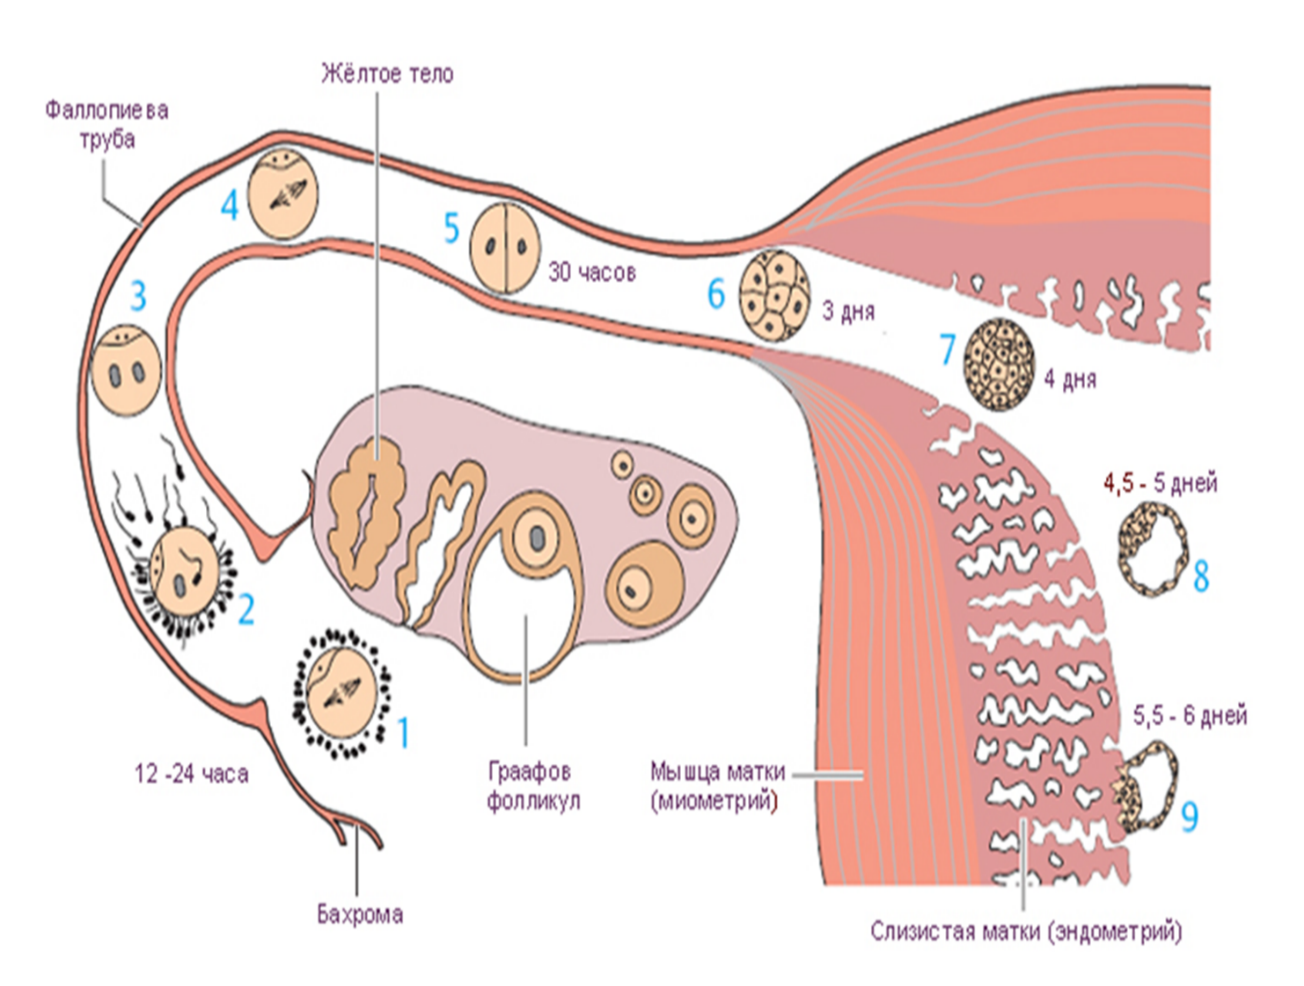

Созревание фолликула в яичнике: этапы и процессы